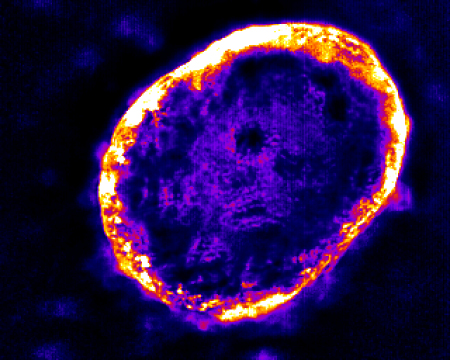

Cellular sphere that is purple and lit throughout by yellow-orange light.

Carbon nanotubes that have infiltrated a tumor give off light indicating the tumor’s permeability, which can be a critical factor in how well cancer drugs will work.

The above image, generated by the lab of Memorial Sloan Kettering pharmacologist Daniel Heller, shows a 3-D breast cancer tumor spheroid — a clump of human cells grown in a flask — that has been infiltrated by carbon nanotubes. These tiny, needle-like particles are about one nanometer (a millionth of a millimeter) thick.

The nanotubes give off light that reveals how permeable, or porous, the tumor is. This light, of infrared wavelength, is invisible to the eye but easily detectable by a special camera, even deep within tissues.

Tumor permeability can be a critical factor in how well a cancer therapy works. Different tumor types have different levels of permeability, depending on the density of the tumor’s extracellular matrix — a collection of molecules secreted by cells that provides structural and biochemical support. The nanotubes easily pass through a loose matrix but are foiled if it is too dense.